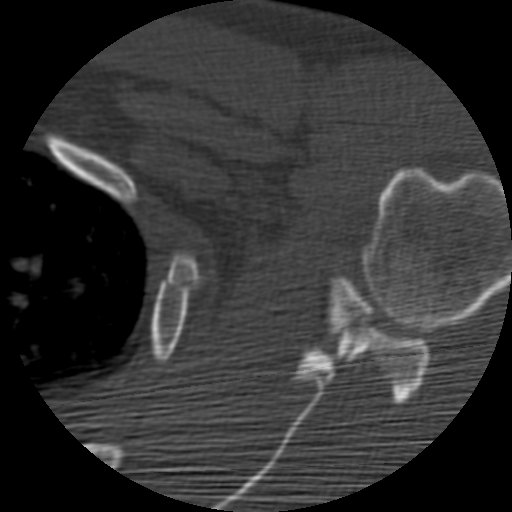

Return to Rib Fracture